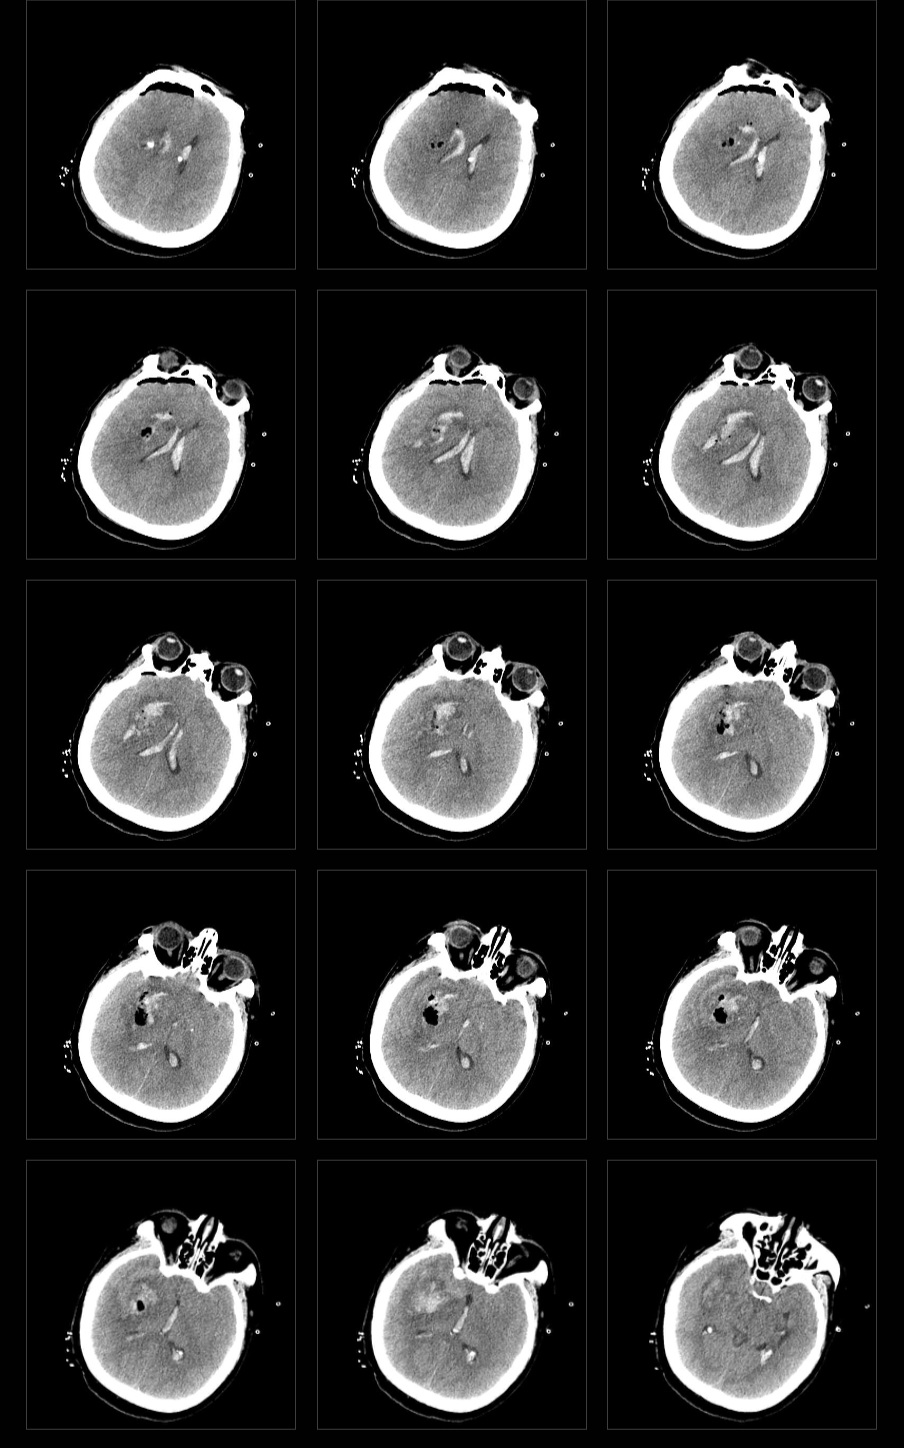

患者为中年女性,突发意识不清入院,外院CT提示右侧基底节出血破入脑室。

术前CT

术中因为考虑到止血问题,没有继续清除脑室内的血肿……好久不用内镜手术确实有点生疏了……

术后CT

术后查体:神志昏迷,刺痛不睁眼,保留气管插管。双侧瞳孔正大等圆,光反应存在。左侧肢体刺痛屈曲,右侧肢体刺痛定位。右侧巴氏征阳性。

术后第三日患者呼唤睁眼,拔出气管插管后可简单对答,右侧肢体遵嘱活动。